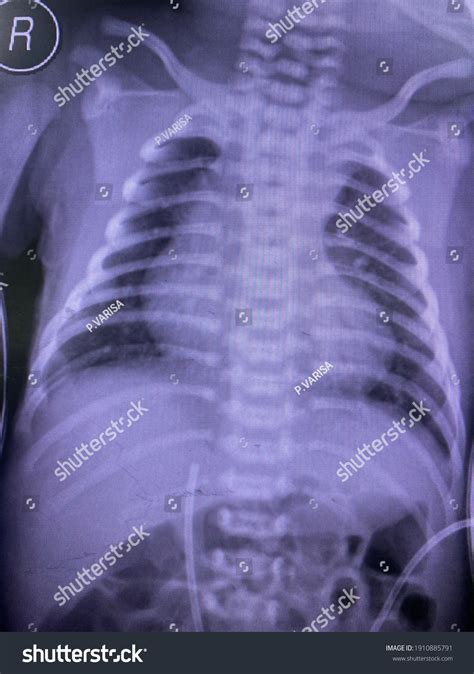

A boot shaped heart is a rare congenital heart defect where the heart takes on an unusual shape, resembling a boot. This condition is often associated with other cardiac abnormalities and can significantly impact an individual's health and quality of life. Understanding the anatomy and physiology of a boot shaped heart is crucial for medical professionals and patients alike.

The heart is a complex organ responsible for pumping blood throughout the body. In a boot shaped heart, the chambers and valves may be malformed or misaligned, leading to various complications. The most common issues include:

• Ventricular Septal Defect (VSD): A hole in the wall separating the heart's lower chambers.

• Atrial Septal Defect (ASD): A hole in the wall separating the heart's upper chambers.

• Pulmonary Stenosis: Narrowing of the pulmonary valve, which controls blood flow from the heart to the lungs.

• Aortic Stenosis: Narrowing of the aortic valve, which controls blood flow from the heart to the rest of the body.

These defects can cause blood to flow inefficiently, leading to symptoms such as shortness of breath, fatigue, and cyanosis (a bluish discoloration of the skin due to lack of oxygen).